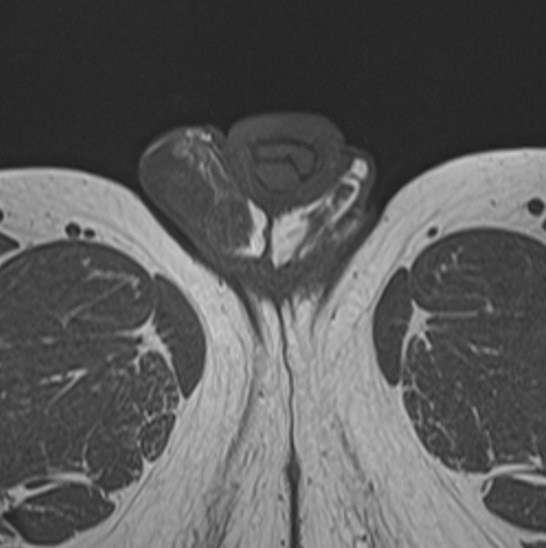

Метод позволяет диагностировать патологию мужских половых желез (яичек), их придатков и семявыносящих протоков. Эти органы, вместе с кровеносными сосудами, лимфатическими протоками и нервами, располагаются в мошонке – мешотчатом образовании из гладких мышц и кожи.

Во время исследования производится послойное сканирование в трех взаимно перпендикулярных плоскостях с шагом от 1 мм, в дальнейшем с помощью инновационных приложений аппарат трансформирует полученные данные в трехмерные изображения. Методика позволяет выявлять структурные изменения органов мошонки на самой начальной стадии. Особенно это важно для диагностики опухолей.

При подозрении на развитие объемных образований, для проведения дифференциальной диагностики, может применяться контрастное усиление. В таких случаях, пациенту внутривенно вводится контрастный препарат, содержащий гадодиамид (соли металла гадолиния), который способен «высвечивать» патологические очаги при попадании в зону действия магнитного поля томографа. С помощью контрастирования удается выявлять опухоли размером от 1 мм. Ранняя диагностика онкозаболеваний позволяет вовремя назначить необходимое лечение.

После того, как исследование окончено, задачей врача является расшифровка полученных снимков. Чаще всего удается определить следующие патологические процессы:

• Аномалии строения органа;

• Злокачественные или доброкачественные новообразования;

• Фиброзные изменения кавернозных тел;

• Сосудистые патологии, в том числе варикоцеле;

• Водянка яичка;

• Наличие абсцесса;

• Пневматоз;

• Склероз яичек;

• Крипторхизм;

• Воспалительные процессы;

• Аденомиоз;